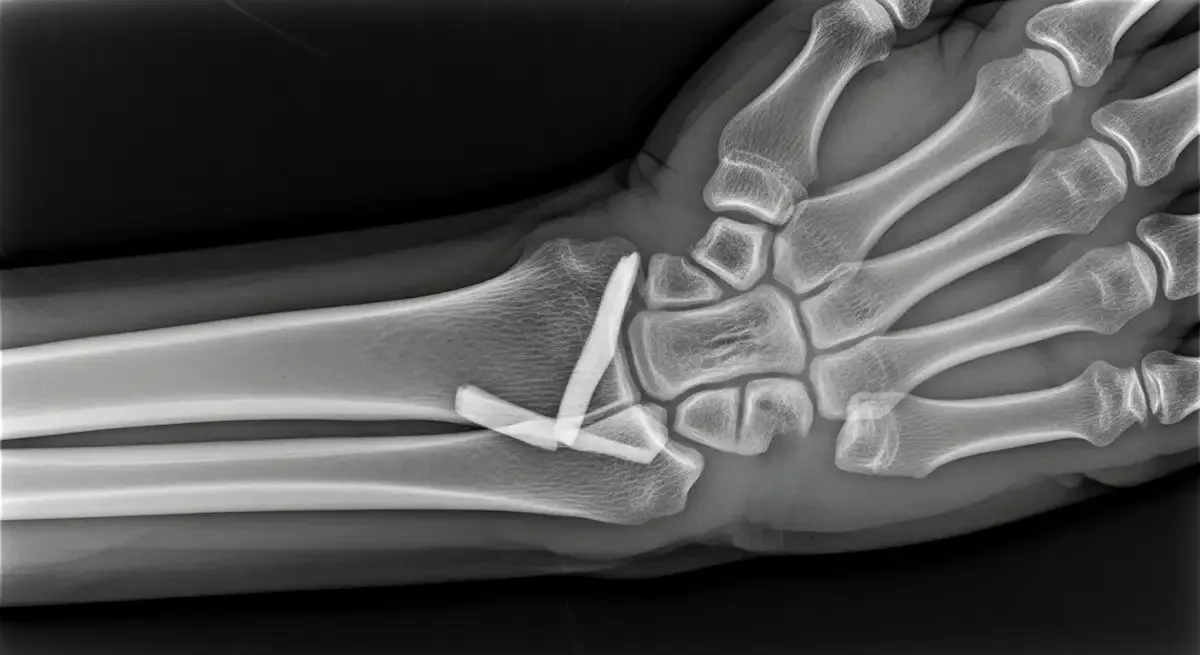

O exame físico identifica a dor localizada e limitação funcional. Radiografias confirmam a fratura de Bennett e avaliam o desalinhamento.

Em casos selecionados, a tomografia ajuda a medir incongruências articulares e planejar o tratamento.

A cirurgia é indicada quando existe instabilidade, subluxação persistente ou degrau articular relevante. O objetivo é restaurar o alinhamento, estabilizar a fratura e preservar a articulação do polegar.

• Redução fechada com fixação percutânea usando fios ou parafusos.

• Redução aberta e fixação interna quando não se obtém alinhamento adequado de modo fechado.